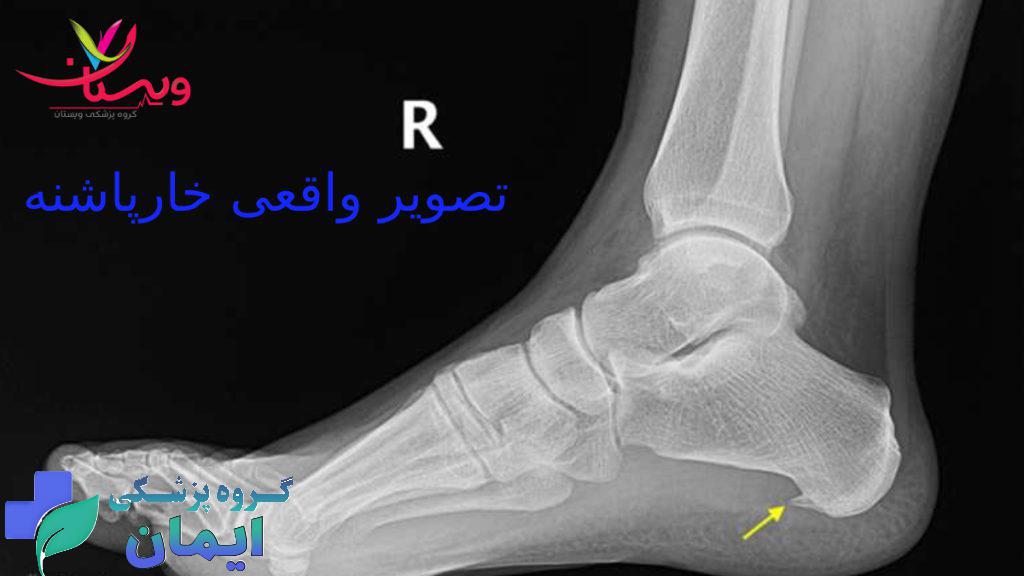

روش های تشخیص خارپاشنه

تشخیص خارپاشنه معمولاً از طریق معاینه بالینی توسط پزشک، بررسی سابقه درد و علائم، و تصویربرداری با اشعه ایکس یا سایر روشهای تصویربرداری انجام میشود. در معاینه بالینی، پزشک به دنبال نقاط دردناک و حساس در پاشنه پا، محدودیت دامنه حرکتی مچ پا، و نحوه راه رفتن بیمار میگردد.

عکس واقعی خارپاشنه